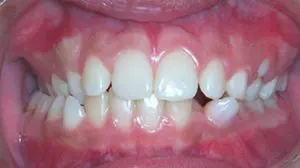

Upper Front Teeth Protrusion

The appearance and function of your teeth are impacted by this type of bite. It is characterized by the upper teeth extending too far forward or the lower teeth not extending far enough forward.